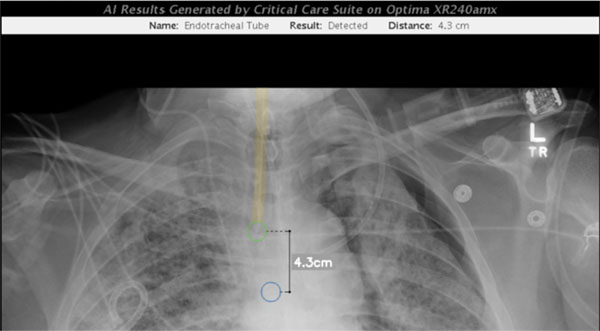

Dr. Mongan shared images (shown below) demonstrating the algorithm identifying a pneumothorax in a recent ICU patient (red annotations were added manually to highlight the findings). Also shown are the results of a separate algorithm measuring the position of the endotracheal tube on the same patient, developed by Valentina Pedoia, PhD, assistant professor and data scientist, Dr. Rachael Callcut, MD associate professor of surgery now at the University of California, Davis, and Sharmila Majumdar, PhD, vice chair of research and executive and scientific director of the ci2, measuring the position of the endotracheal tube on the same patient. Other key participants were radiologist Thienkhai Vu, MD and fellow Rutwik Shah, MD and other investigators from the CDHI. Note, all patient data has been removed.